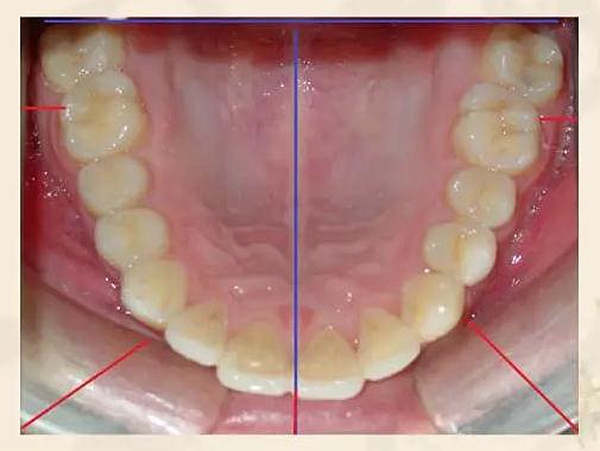

圖文詳解正畸的拍照細(xì)則 科貿(mào)嘉友收錄

來(lái)源:李筱筱 正畸學(xué)會(huì)